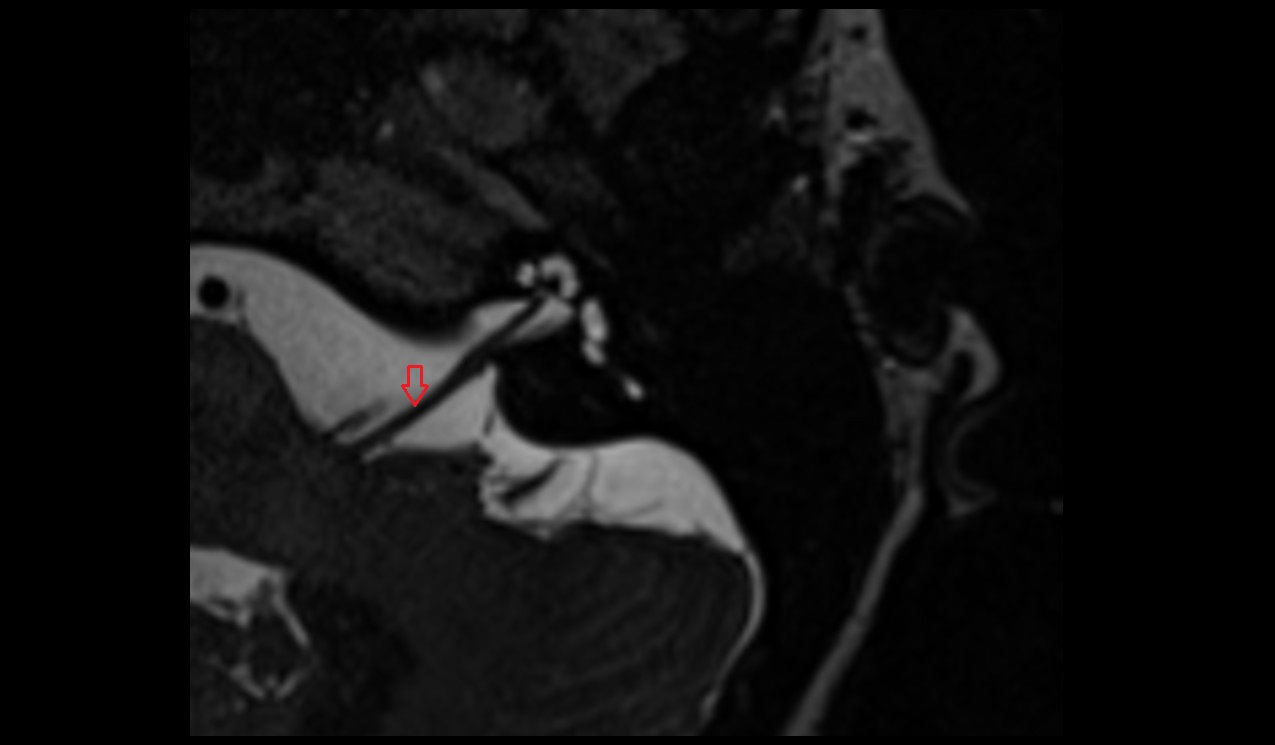

- Temporomandibular joint

- Articular disc of temporomandibular joint

- Mandibular condyle

- Mandibular fossa